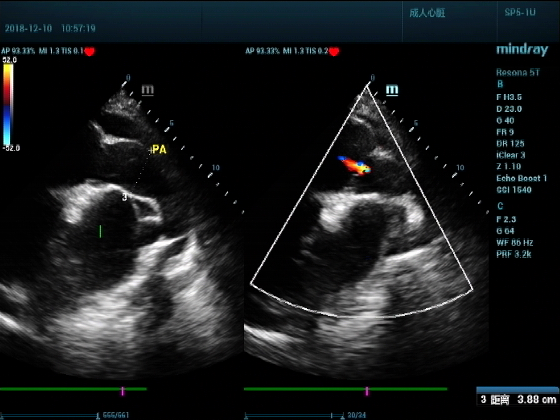

男,81岁,全身浮肿来住院

超声可见:左房,右房,右室明显增大,主肺动脉及右肺动脉增宽,二尖瓣中度反流,三尖瓣重度反流,肺动脉轻度高压,心律不齐

心包积液盆腔积液。淤血性肝增大,肝静脉增宽。(右心衰声像改变)